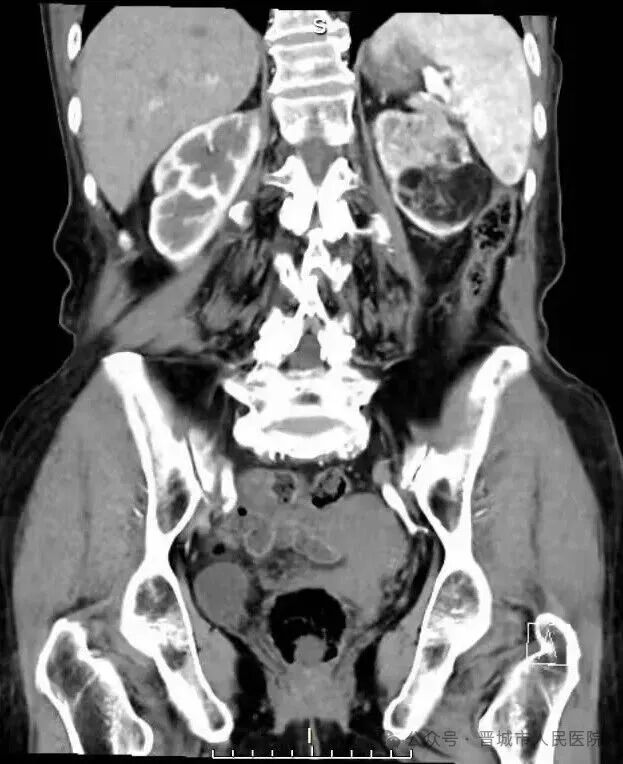

据了解,患者因体检发现左肾占位20余天入院,外院检查提示左肾肿物大小约45*55*98mm,接近十公分的肿瘤体积给治疗带来了极大挑战。更为棘手的是,患者年事已高,体质薄弱且营养状况欠佳,腹壁肌肉薄弱导致手术戳卡固定困难,传统腹腔镜手术操作空间受限、难度极高,而患者及家属保肾意愿十分强烈。

术前,团队还组织多学科病例讨论,针对肿瘤位置深、血供丰富的特点,量身制定个性化手术方案,充分预判术中可能出现的风险并制定应对策略,将微创技术与精准医疗理念深度融合。